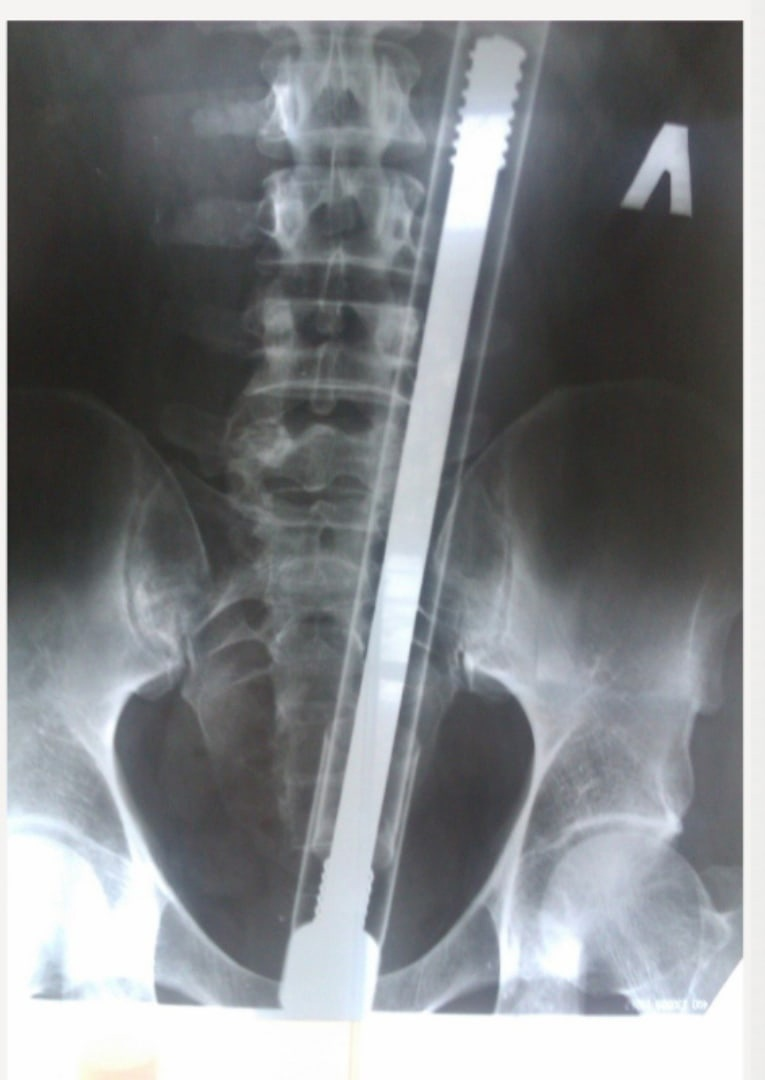

Насос от мопеда

Прямая кишка обладает свойством затягивать в себя различные предметы. Человек, поступивший в больницу, видимо не знал о такой удивительной способности своего организма. Врачам парень сказал, что случайно напоролся, но мы то все понимаем. И остаётся один не решенный вопрос: "почему парень выбрал именно насос?"